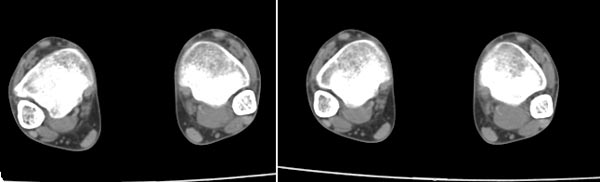

x线检查月前片示双踝关节骨质未见明显异常。一月后肿胀大部消失,疼痛稍有好转,摄片示两侧骨下段条带状高密度影,边界尚清。ct扫描示两侧胫骨下段骨皮质增厚不明显,髓腔内密度显示磨玻璃样增高,髓腔显示狭窄。

x线检查一个月前示双踝关节骨质未见异常。一个月后肿胀大部消失,疼痛稍有好转,摄片示两侧胫骨下段横行条状高密度影,边界较清。ct扫描示:两侧胫骨下段未见骨皮质增厚,两胫骨下段近骨端处可见骨小梁增粗但纹理尚清晰,未见明显骨质破坏,邻近关节及关节囊未见明显异常,软组织内未见异常.综上所诉考虑1.低毒感染所致,2.假性痛风

x线片表现为双侧胫骨下端粗条状磨玻璃样增高密度影,并可见骨皮质稍不连续。ct表现为双侧胫骨下端髓腔内磨玻璃样增高密度影,未见明显骨皮质不连续(可能与扫描体位有关)。